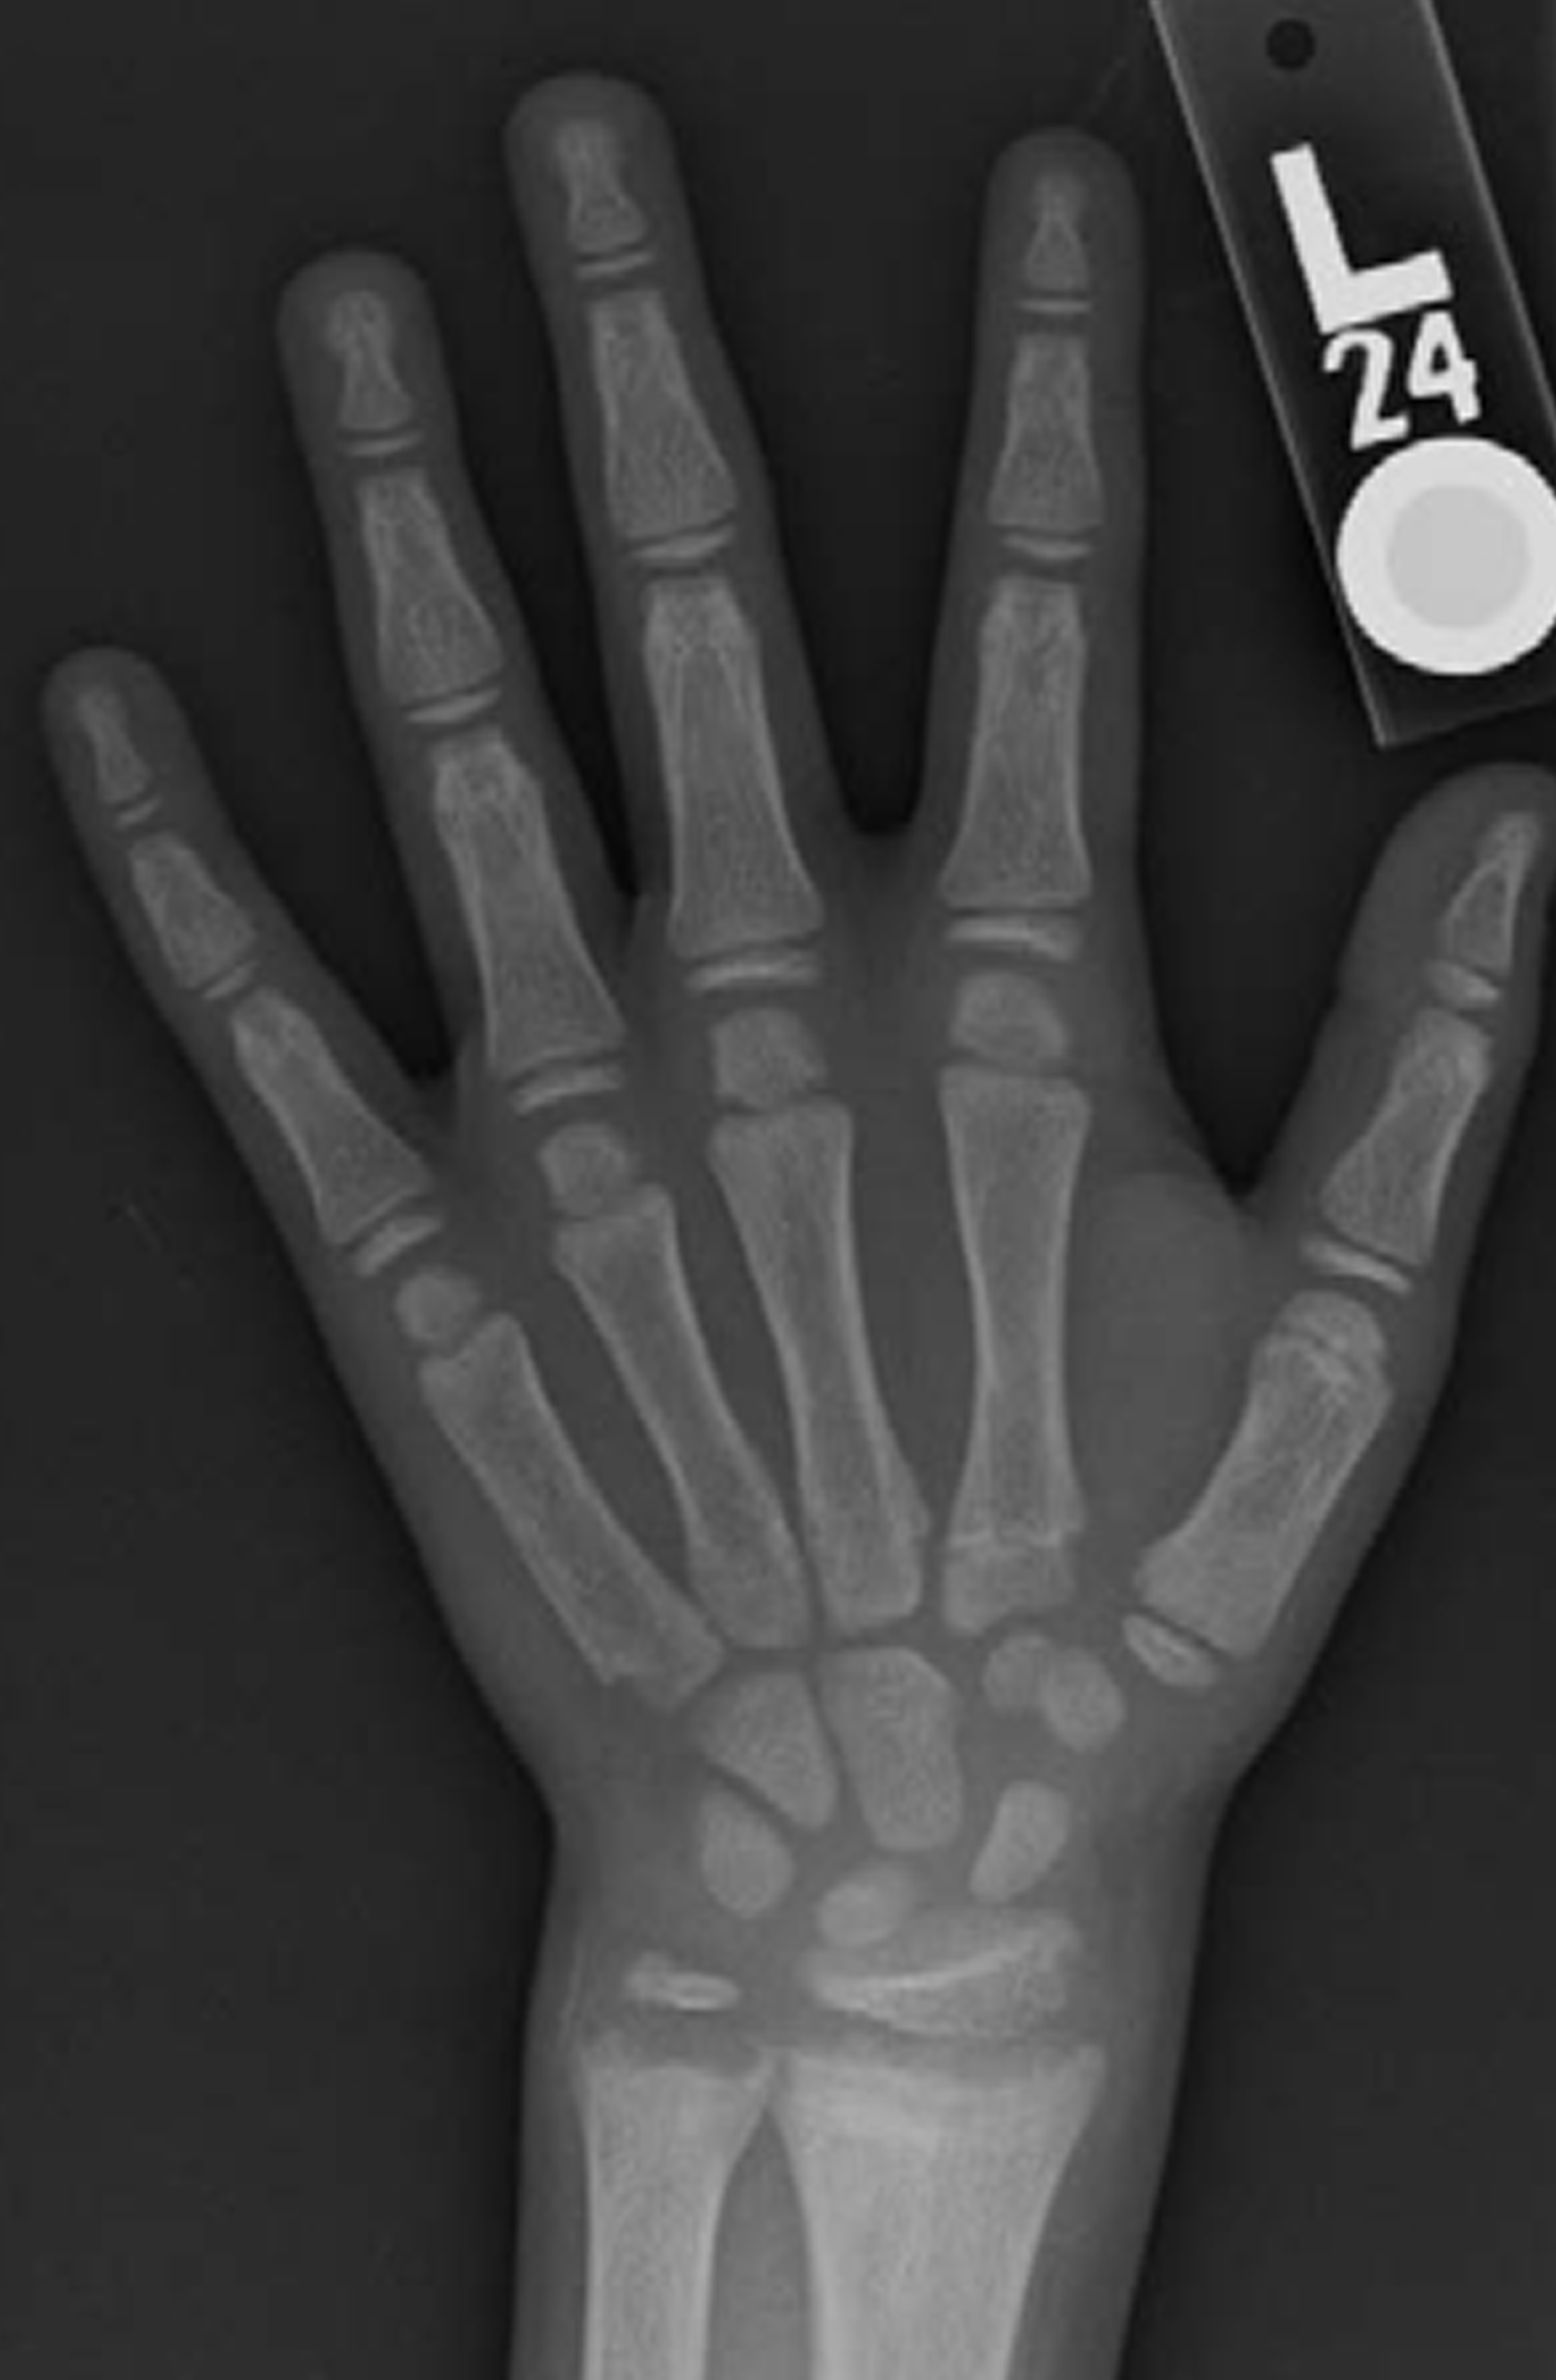

Select the wrist with the most severe signs of XLH.

In this case, the left wrist shows more severe signs of XLH. There is a greater degree of lucency in both the radius and ulna of the left wrist.

Now, we’ll score the radius and the ulna separately and add their scores together to calculate the total wrist score.

The radius shows lucency of the metaphyseal margin, but it has a smooth margin with no fraying or irregularity, so it’s scored as a 0.5. The ulna has a widened growth plate and irregularity of the metaphyseal margin, but does not show signs of concave cupping, so it’s scored as a 1. Adding these two scores together, we get a total score of 1.5 for the wrist.